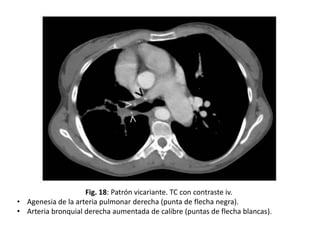

Patrón de vascularización vicariante

• Consiste en la visualización de la circulación

arterial bronquial en la radiografía simple de

tórax, que en condiciones normales no se

identifica.

• Cuando las arterias bronquiales se hacen

patentes en los campos pulmonares se perciben

como una red anárquica de líneas en

contraposición a la disposición normal de los

vasos pulmonares, que sigue una distribución

arboriforme

Fig. 18: Patrón vicariante. TC con contraste iv.

• Agenesia de la arteria pulmonar derecha (punta de flecha negra).

• Arteria bronquial derecha aumentada de calibre (puntas de flecha blancas).